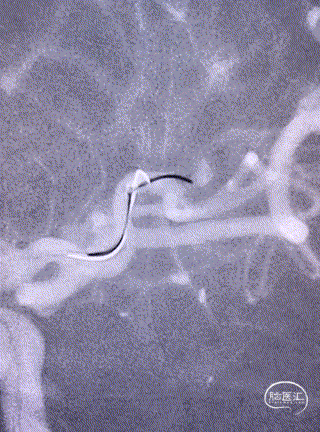

小血管血栓取栓病例

一例左侧大脑中动脉M3段闭塞远端

抽吸导管血管再通治疗

作者:高军、温昌明